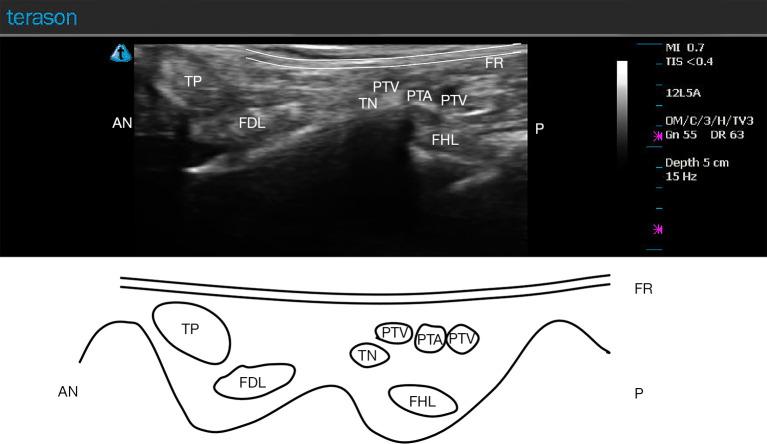

Tarsal tunnel syndrome (TTS) is a condition in which the tibial nerve (TN) (or its terminal branches) is compressed by the flexor retinaculum (FR) and the deep fascia of the abductor hallucis muscle at the tarsal tunnel, causing symptoms that negatively impact the patient's quality of life, including numbness, a sensation of a foreign object, coldness, and pain. FR release via microtrauma using needle-knife has proven to be effective in China and is widely used by clinicians. The traditional acupotomy, however, is the "blind knife" treatment, which cannot guarantee patient safety due to risk of injury to important structures, particularly the neurovascular bundle. Compared with the conventional treatments, ultrasound-guided percutaneous FR release possesses noteworthy advantages including high efficacy and safety.

跗管综合征(TTS)是一种胫神经(TN)(或其终末分支)在跗管处被屈肌支持带(FR)和拇展肌深筋膜压迫的病症,会引发对患者生活质量产生负面影响的症状,包括麻木、异物感、发冷和疼痛。在中国,使用针刀通过微创伤进行FR松解已被证明是有效的,并且被临床医生广泛应用。然而,传统针刀是“盲刀”治疗,由于存在损伤重要结构(特别是神经血管束)的风险,无法保证患者安全。与传统治疗方法相比,超声引导下经皮FR松解具有显著优势,包括高效性和安全性。